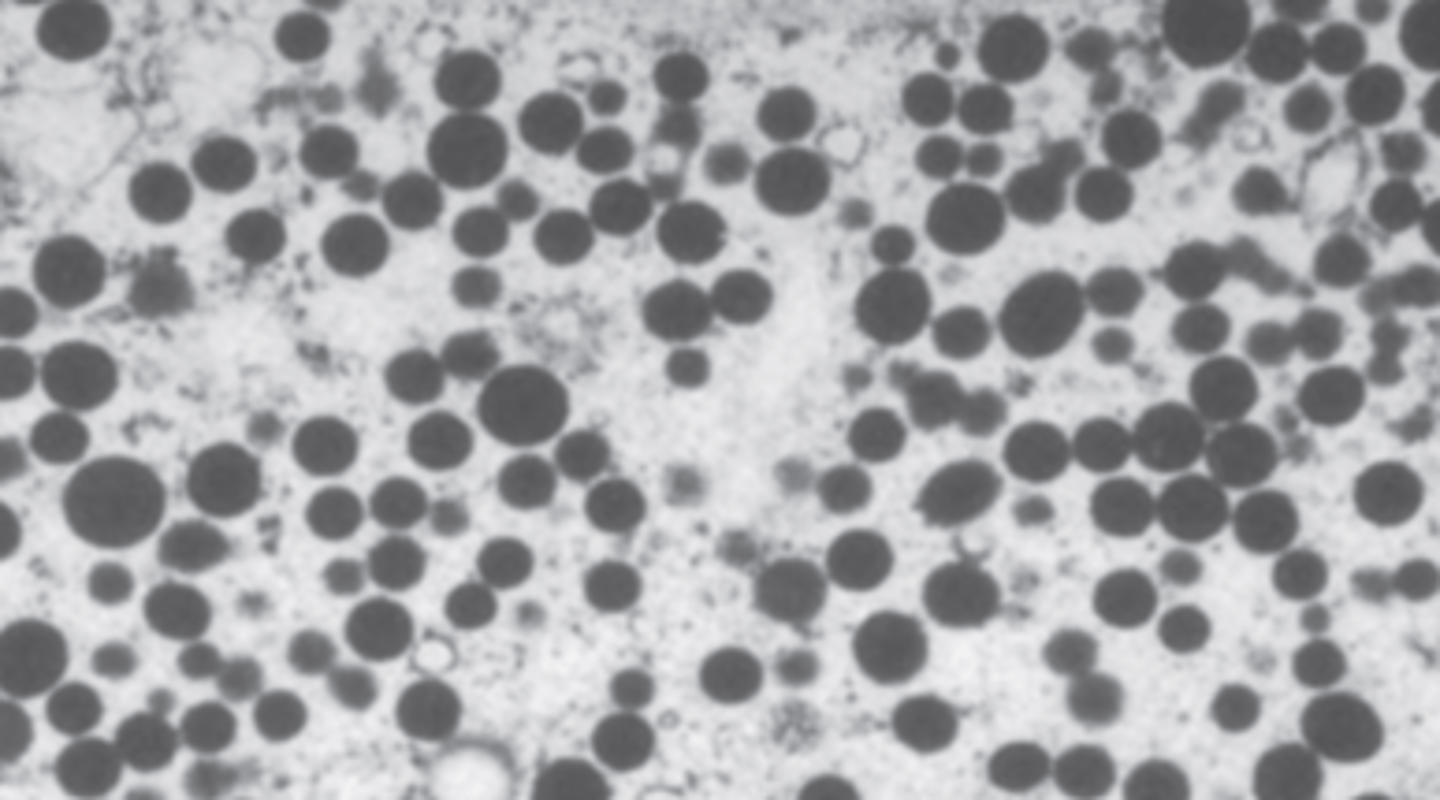

A 54-year-old man presents with a 9-month history of progressive skin pigmentation. He passes large amounts of urine and is always thirsty. His father died of liver cancer. Physical examination reveals a dark skin color and an enlarged liver. Laboratory studies show normal serum levels of corticotropin. A glucose tolerance test indicates chemical diabetes. A liver biopsy stained with Prussian blue is shown in the image. If untreated, which of the following conditions is most likely to develop in this patient?

(A) Acute hepatitis

(B) Addison disease

(C) Cholangiocarcinoma

(D) Cholelithiasis

(E) Hepatocellular carcinoma